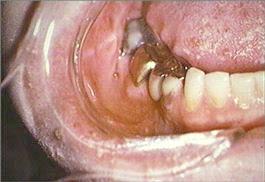

The skin on the right side of the face is erythematous and contains small vesicles and ulcers. Small ulcers are present on the right dorsum of the tongue, mucobuccal fold and the gingival papilla between the mandibular right central and lateral incisors. The mandibular right first and second molars and the surrounding mucosa are painful to palpation. The periapical radiograph reveals no evidence of periapical disease. The mandibular right first and second molars are responsive to pulp testing and give no evidence of pulpitis. No palpable lymph nodes are present.

mandibular anterior teeth and gingiva right mandibular teeth and mucobuccal fold